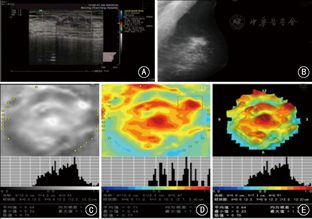

电阻抗断层扫描仪MEIK设备,主要由一主体机、256电极组成的电极面板和一远端电极组成;图1示EIT技术检测患者双侧乳腺影像的各种数据信息,从患者基本信息,影像深度、电导率异常区域、电导率曲线、电导率数据值及双侧电导率分布差异来解析受检者乳腺图像;图2示1例70岁女性乳腺癌患者术前影像资料对比:A: 超声示左乳外上一形态不规则、低回声肿块,边界不清,内可见丰富血流信号,B: 钼靶侧斜位示左乳外上可见类结节影,边缘欠光整,其内可见粗大钙化灶,C~E: MEIK黑白、彩色及三维图像示左乳外上一椭圆形高电导率区,大小2.7 cm×2.4 cm,中心区域最高电导率达1.04,周围组织结构受压;图3示1例44岁女性乳腺纤维腺瘤患者术前影像资料对比:A: 超声示左乳9:00~10:00点方向低回声,大小3.1 cm×0.6 cm,边界清,内回声均匀,未见血流信号;B: 钼靶侧斜位示左乳不均匀致密性腺体,乳腺增生,可见良性钙化;C~E: MEIK黑白、彩色及三维图像示左乳10:00点方向一片状高电导率区,中心区域电导率达0.77,周围组织呈超阻抗区,未见明显受压。